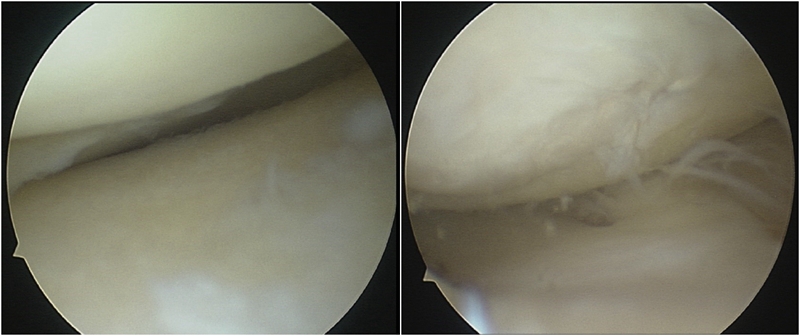

术中关节镜证实外侧软骨良好,取出游离体,内侧清理后行胫骨高位截骨术。

内侧软骨负重区II-III级病变

因此,术中用关节镜在髁间窝和髌上囊分别取出了两枚游离体,术中也验证了MR显示的外侧关节面水肿区不是位于外侧间室的负重区,关节镜下外侧软骨为全层软骨,软骨退变区位于股骨滑车沟外侧近潮线处,内侧软骨磨损,部分裸露。故在内侧清理后加做HTO,将力线调整至55%。术者相信这是最利于患者的治疗选择。